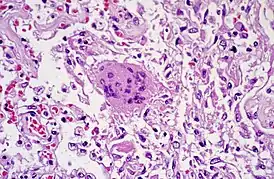

Патологическая анатомия

Обнаруживаются диффузное повреждение лёгочных альвеол, десквамация пневмоцитов, образования гиалиновых мембран и воспалительные инфильтраты[21].